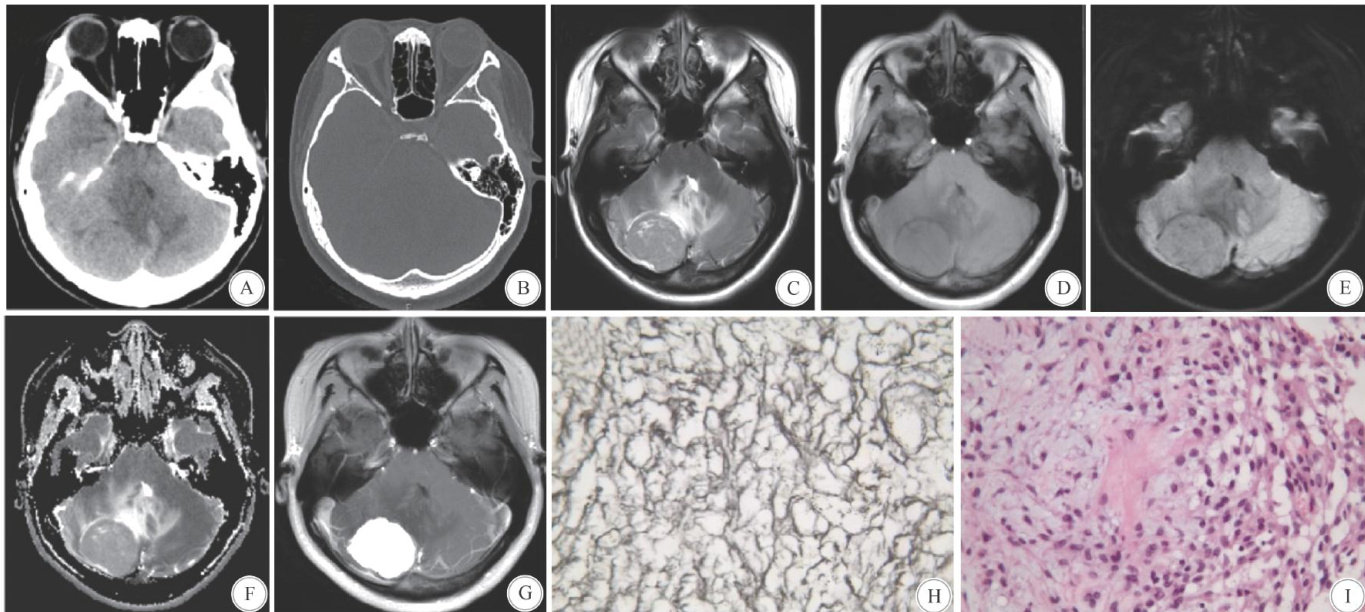

Abstract: ObjectiveTo investigate the imaging and pathological characteristics of intracranial mesenchymal tumor(IMT)harboring FET-CREB fusion-positive.MethodsThe CTand MRI imaging features,histomorphology, immunophenotype,and molecular genetic characteristicsof an IMT positive forFET-CREB fusion patient were analyzedretrospectively.Therelevantliteraturewerealsoreviewed.ResultsThetumorwaslocated in theright posteriorcranial fossa,exhibitingawell-defined shape.CTshowedarelativelyhomogeneous,ovaloid,isodensemass with significant peritumoral edema and mass effect.MRI revealeda tumor with heterogeneous signal intensity, demonstrating prominent enhancement post-contrastadministration,accompanied bypatchy non-enhancing areas.No dural tail sign was observed.Initial diagnosison imaging wasmeningioma orsolitary fibroustumor. Histopathologically,the tumorcelswerearranged ina lobularpattern withinamyxoid matrixrich inmucin.The tumortissue was highly vascularized and showed focalcollagenization.Immunohistochemistryshowed the tumorcells were positive for EMA,VIM,H3K27me3,and INI1.Focal positivity was observed for S1O,SSTR2,DES,CD99, CD68,CD63,and EGFR.The pathological findings were consistent with a myxoid tumor. Subsequent molecular genetictesting confirmedanintracranial mesenchymal tumor positiveforFET-CREB fusion.ConclusionsIMTs with FET-CREB fusion-positive can present with atypical imaging features.The definitive diagnosisrelieson comprehensive histopathological evaluation supplemented by molecular genetic testing.